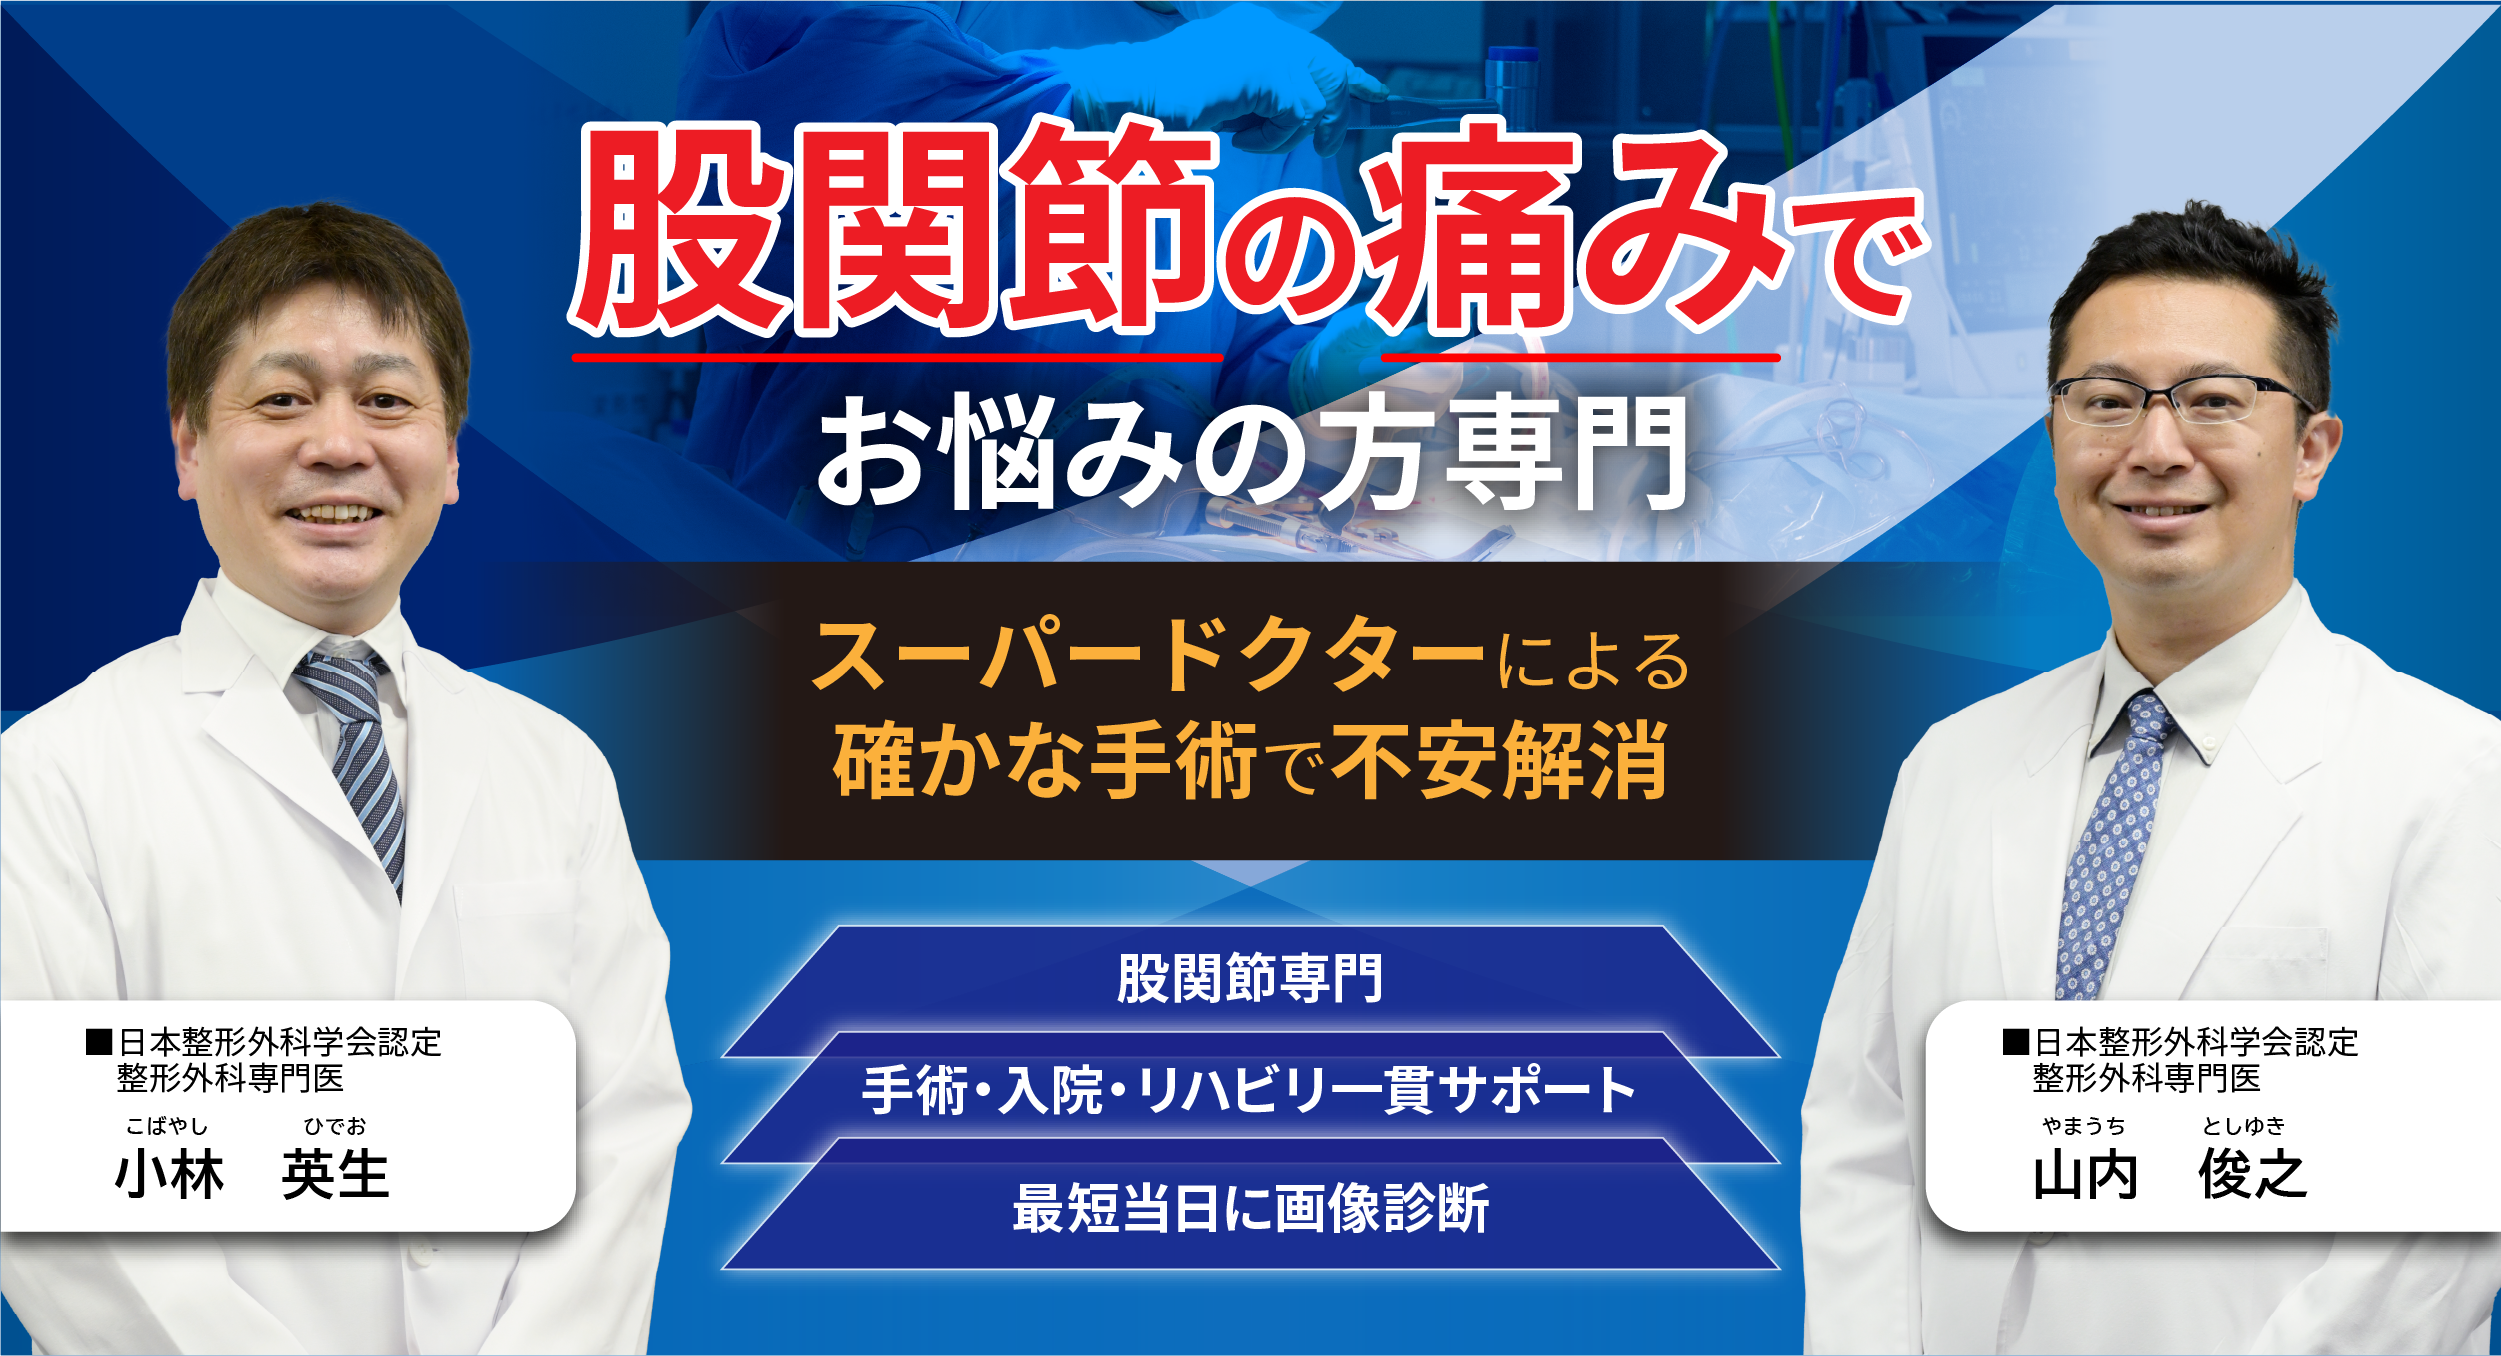

当院が選ばれる 3つの理由

股関節の

プロフェッショナル

当院の医師は股関節治療に豊富な経験と高い技術を持つ専門家です。人工股関節置換術では、筋肉を切らない最小侵襲手術(MIS)を採用し、傷口が小さく痛みも少ないため、患者さまの身体的負担を大幅に軽減します。

診察・手術・リハビリ

まで一貫サポート

診察では患者さま一人ひとりに合わせた最適な治療をご提案します。手術を選ばれた場合も、入院・手術・リハビリ、さらに退院後のアフターケアまで、私たちが責任を持って一貫してサポートいたします。

当日に診断、

結果報告

当院は透視機能付きレントゲン、CT、MRI、運動器超音波など最新の検査機器を完備。来院当日に精密検査を行い、原因を迅速かつ正確に特定します。検査後は専門医が丁寧に説明し、最適な治療方針をご提案します。

医師紹介

こんにちは。当院で膝・股関節疾患の診療を担当しております、小林英生と申します。

これまで順天堂大学および関連病院で研鑽を積み、フランスへの留学も経験したのち、現在は賛育会病院にて人工関節センター長を務めています。

海外では「痛みなくスポーツを楽しむため」に人工関節置換術を選ぶ方が増えており、日本でも同じように、関節の痛みに悩む方々にとって人工関節という選択肢がもっと身近になるべきだと考えています。

専門医として、ひとりひとりの患者さまが痛みのない日常を取り戻せるよう、これからも真摯に向き合ってまいります。

当院で膝・股関節の診療を担当しております、山内俊之と申します。

慶應義塾大学病院および関連病院にて、これまで多くの患者さまの下肢疾患と向き合い、診療を行ってまいりました。

関節の痛みは、痛みを感じる部位と、実際に原因となっている部位が異なることも少なくありません。たとえば股関節が痛いと思っていても、膝や腰が関係しているケースもあります。

そうした複雑なケースでも、医学的な視点から丁寧に診察を重ね、正確な診断と的確な治療につなげることを大切にしています。

患者さま一人ひとりの背景や生活に寄り添いながら、痛みの軽減と生活の質の向上に全力で取り組んでまいります。